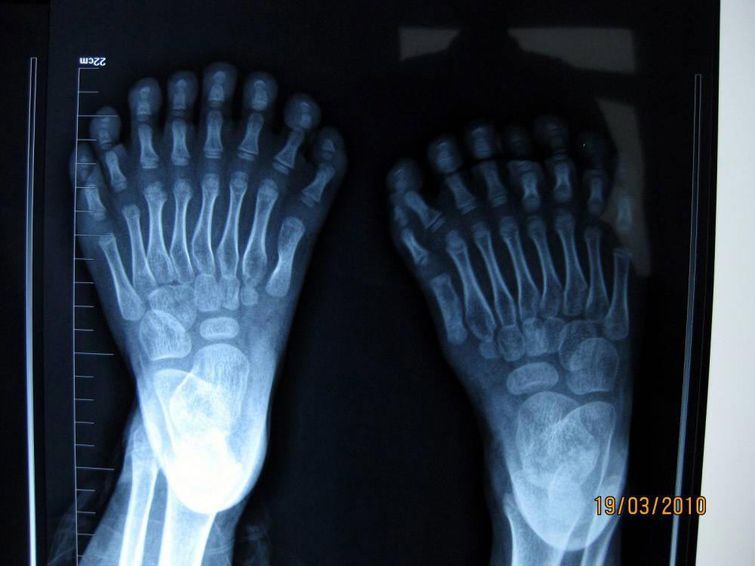

Рентгеновские снимки 6-летнего мальчика, сделанные в больнице Шэн Цзин, Китай

Этот мальчик установил рекорд по количеству пальцев, которых на его руках и ногах насчитывается ровно 31